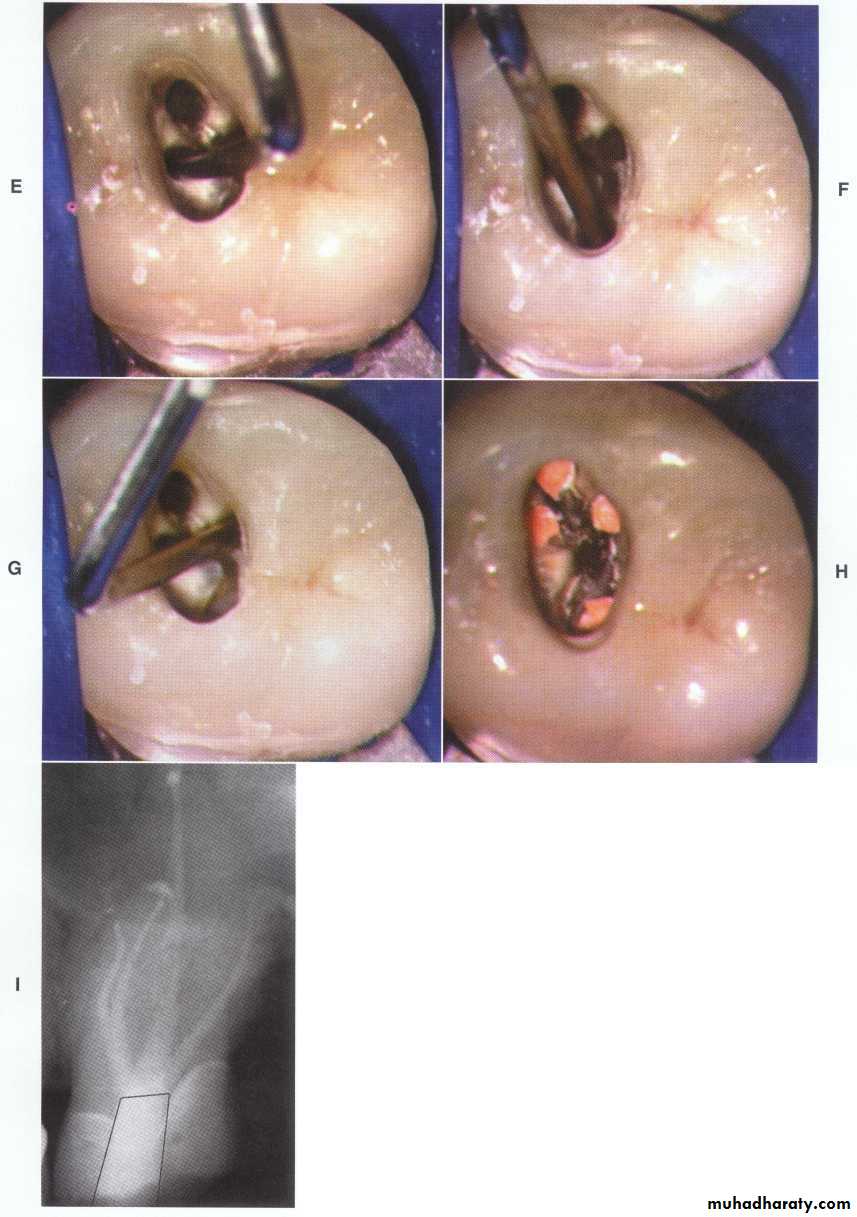

Error in access opening in max. ant teethA.PERFORATION: at the labiocervical caused by failure to complete convenience extension toward the incisal, prior to the entrance of the shaft of the bur.B.GOUGING: of the labial wall caused by failure torecognize the 29-degree lingual-axial angulation of the tooth.

C. GOUGING: of the distal wall caused by failure to recognize the 16-degree mesial-axial inclination of the tooth. D.PEAR-SHAPED PREPARATION: of the apical canal caused by failure to complete convenience extensions. The shaft of the instrument rides on the cavity margin and lingual “shoulder.” Inadequate débridement and obturation ensure failure.

E.DISCOLORATION: of the crown caused by failure to remove pulp debris. The access cavity is too far to the gingival with no incisal extension.F. LEDGE: formation at the apical-distal curve caused by using an uncurved instrument too large for the canal. The cavity is adequate.

G.PERFORATION: at the apical-distal curve caused by using too large an instrument through an inadequate preparation placed too far gingivally. H.LEDGE: formation at the apical-labial curve caused by failure to complete the convenience extension. The shaft of the instrument rides on the cavity margin and “shoulder.”